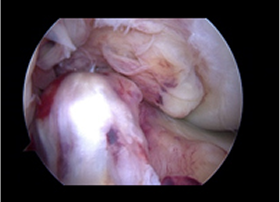

치료 전 붉게 패여 손상된 연골이 치료 후 정상적으로 회복된 모습

before img after img